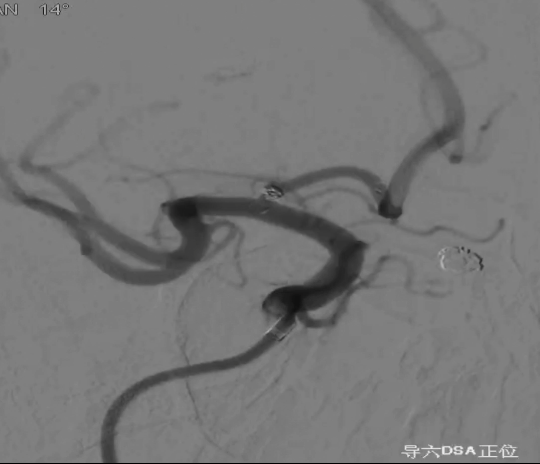

术后正侧位造影:Raymond Ⅲ级

术后支架重建:支架打开良好,近端Marker位于颈内动脉分叉处

继续填入Target 1.5/2弹簧圈成篮,后完全释放支架,其近端位于颈内动脉分叉处,远端位于A1远端。